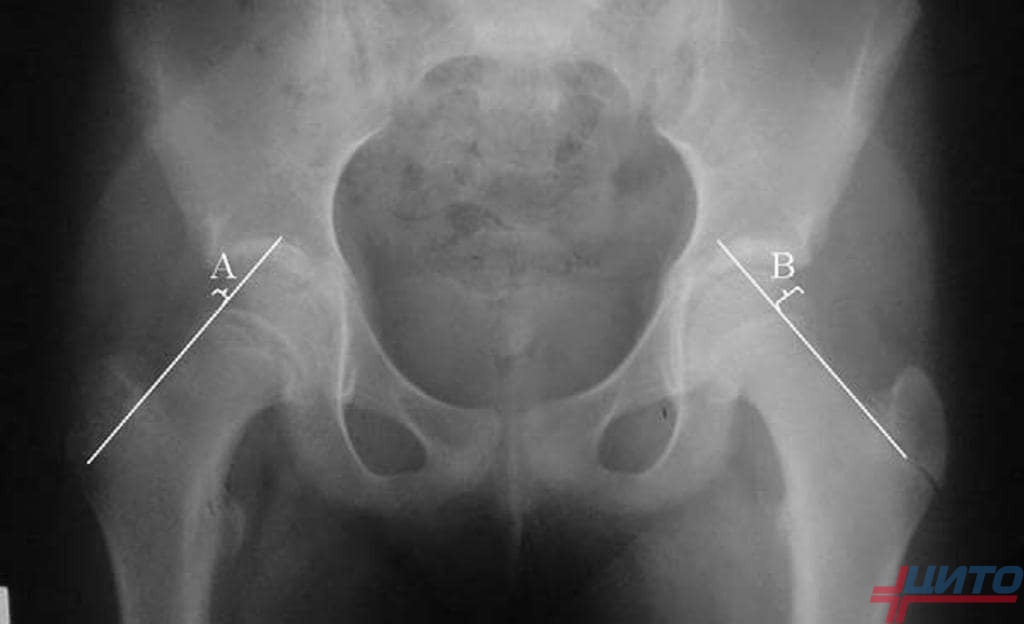

Рентгенограмма пациента К. 9 месяцев, диагноз: Эпифизарная дисплазия правого тазобедренного сустава.

Клиническая картина у детей с болезнью Пертеса и Майера практически одинакова. Однако, у пациентов с болезнью Майера ведущие симптомы менее выражены. Болезненные ощущения в паховой области могут беспокоить около 2 – 3 месяцев и спонтанно прекратится. Нарушение походки – не постоянная хромота, так же носит кратковременный характер, без ограничений движений в пораженном тазобедренном суставе.

Для уточнения диагноза и тактики лечения врач – ортопед обязан рекомендовать рентгенологическое обследование и КТ – исследование. Рентгенологическая картина этих заболеваний в начальных стадиях очень схожа. Уточнить объем, расположение и глубину остеонекроза сможет только КТ – исследование. Его очаг чаще расположен в центральной или передней части головки бедра, с глубиной поражения 15 – 25 %, в сочетании со снижением высоты головки бедренной кости.

Рентгенограмма и КТ – исследование пациента К. 4 года, диагноз: болезнь Майера справа до начала лечения (25% остеонекроза пораженной головки).